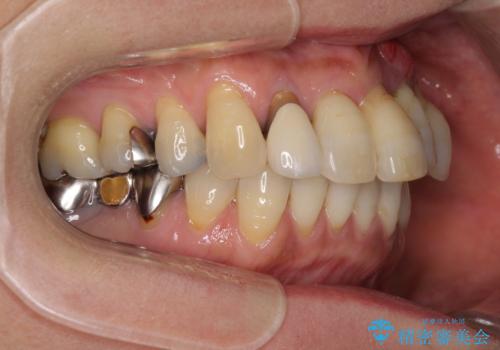

前歯のみならず、奥歯の銀歯や下顎前歯のデコボコなど、色々と気になる部分を治したいとのことでした。

下顎と上顎臼歯部については矯正治療を行い、奥歯の欠損部位はオールセラミックブリッジを、その他の銀歯はセラミックインレーなどにより治療を行うこととしました。